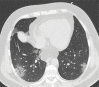

Chest CT has a potential role in the diagnosis, detection of complications, and prognostication of coronavirus disease 2019 (COVID-19). Implementation of appropriate precautionary safety measures, chest CT protocol optimization, and a standardized reporting system based on the pulmonary findings in this disease will enhance the clinical utility of chest CT. However, chest CT examinations may lead to both false-negative and false-positive results. Furthermore, the added value of chest CT in diagnostic decision making is dependent on several dynamic variables, most notably available resources (real-time reverse transcription-polymerase chain reaction [RT-PCR] tests, personal protective equipment, CT scanners, hospital and radiology personnel availability, and isolation room capacity) and the prevalence of both COVID-19 and other diseases with overlapping manifestations at chest CT. Chest CT is valuable to detect both alternative diagnoses and complications of COVID-19 (acute respiratory distress syndrome, pulmonary embolism, and heart failure), while its role for prognostication requires further investigation. The authors describe imaging and managing care of patients with COVID-19, with topics including (a) chest CT protocol, (b) chest CT findings of COVID-19 and its complications, (c) the diagnostic accuracy of chest CT and its role in diagnostic decision making and prognostication, and (d) reporting and communicating chest CT findings. The authors also review other specific topics, including the pathophysiology and clinical manifestations of COVID-19, the World Health Organization case definition, the value of performing RT-PCR tests, and the radiology department and personnel impact related to performing chest CT in COVID-19. ©RSNA, 2020.